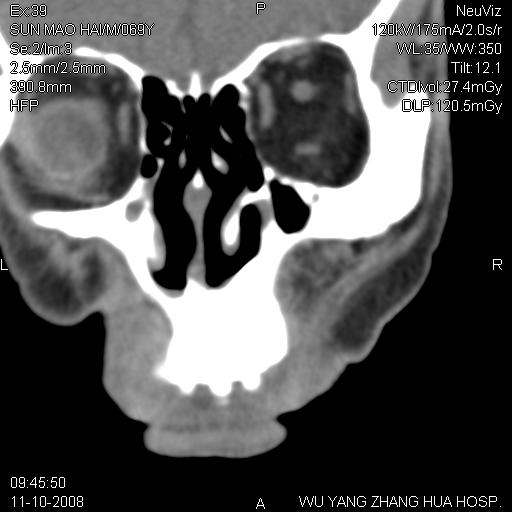

标题: CT16568:右面部瘘管半年余,无其它不适.

考虑右上颌异位齿(或斜向阻生齿)并根尖脓肿。

右上颌异位齿(或斜向阻生齿)

1.右上颌异位齿

2.右上颌化脓性骨髓炎